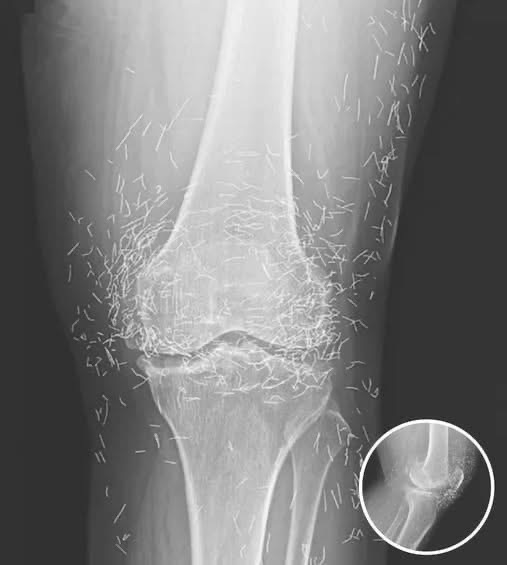

Doctors in South Korea were stunned after a routine knee X-ray on a 65-year-old woman revealed hundreds of tiny gold needles embedded deep in her tissue. What began as a simple check for arthritis pain turned into one of the most unusual medical cases ever recorded.

The woman had suffered from chronic osteoarthritis for years — a condition that causes cartilage and bone to deteriorate, leading to swelling, stiffness, and pain. After standard medication failed to help and caused stomach side effects, she turned to acupuncture, a popular alternative therapy in Asia.

But unlike typical acupuncture treatments, where the needles are removed after each session, her practitioner left the gold needles inside her body — a practice some believe provides ongoing stimulation to relieve pain.

Medical experts, however, warn that this approach is highly dangerous. According to radiology specialists, leaving foreign objects under the skin can lead to inflammation, infection, abscesses, and even interfere with future medical imaging. In extreme cases, it could make procedures like MRI scans life-threatening, since the magnetic field might cause the metal fragments to shift or pierce internal tissue.

Despite the risks, gold thread acupuncture is still practiced in parts of Asia, especially for treating joint problems. Supporters claim it offers long-term relief, though scientific proof remains limited.